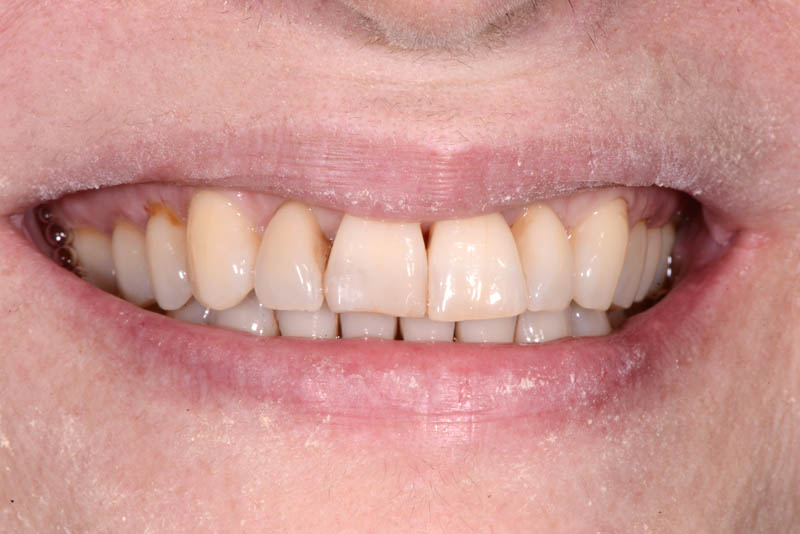

The healing has now reached a 5-year follow-up.

The patient is absolutely delighted with the outcome, but I have repeatedly (and unsuccessfully) encouraged her to undergo a small additional graft to address the minor residual recession on tooth 21.

I even offered to perform the graft free of charge, but she declined.

But then, is it really in the patient’s best interest to undergo another surgical procedure just to fulfill my personal desire for a perfect result?

Even if imperfect, I’m sharing this case.

but it was undoubtedly the best choice for the patient.